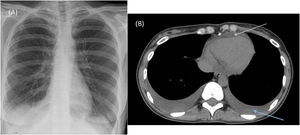

Chest X-ray in the emergency room showed blunting of both costophrenic angles consistent with bilateral pleural effusion (Fig. 1A).

(A) Anterior-posterior chest X-ray at admission showing right pleural effusion and left costophrenic angle blunting. (B) Chest computed axial tomography showing bilateral pleural effusion and pericardial effusion (upper arrow indicates pericardial effusion and the right arrow indicates pleural effusion).

A chest computed tomography angiogram conducted to rule out pulmonary thromboembolism confirmed moderate bilateral pleural effusion with bibasilar and middle lobe atelectasis (Fig. 1B). This was confirmed on chest ultrasound that also ruled out vascular involvement.